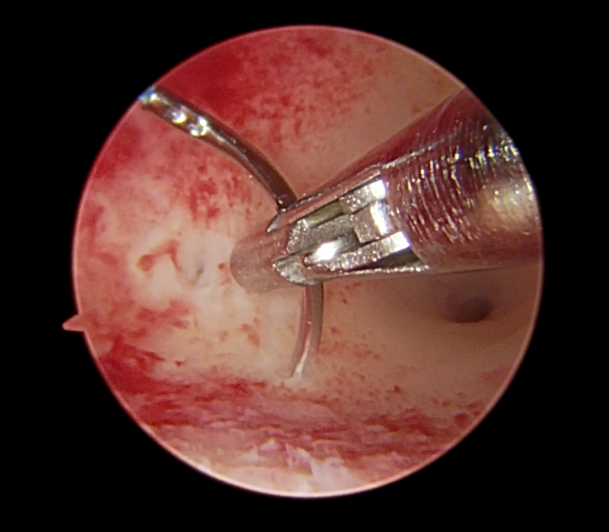

曼月乐环缝合固定术早期主要选择25-26Fr大口径冷刀器械配合持针器推结器进行手术操作,手术效果良好(图1),但是使用25-26Fr大口径冷刀器械往往需要扩宫至9mm-10mm,对宫颈准备要求较高。

图1